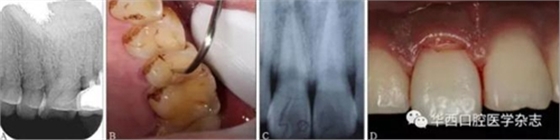

(3)X線片結(jié)果具有隱蔽性,需仔細(xì)結(jié)合臨床檢查進(jìn)行判斷。如圖3所示,X線片未見折裂線(圖3A),而臨床檢查可見明顯的縱折(圖3B);有時(shí)X線片僅顯示1條折裂線(圖3C),而臨床檢查發(fā)現(xiàn)為復(fù)雜冠根折(圖3D)。

A:X線片未顯示根折;

B:臨床檢查可見明顯根折;

C:X線片僅顯示1條唇側(cè)牙折線,舌側(cè)折裂線不清晰;

D:臨床檢查可見右側(cè)上頜中切牙出現(xiàn)明顯冠根折。

圖 3 X線片與臨床檢查對(duì)比結(jié)果